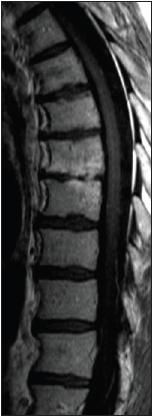

The patient was admitted to the general medicine service for further investigation of his progressive back pain of unclear cause. MRI of the thoracic spine was performed, which showed spondylodiscitis at the level of T7-8 (Figure 1). On day 2 of hospitalization, the patient's temperature spiked to 38.4C (101.1F). Two sets of blood cultures grew viridans streptococci, which were sensitive to ceftriaxone (minimal inhibitory concentration [MIC], 0.25 ?g/mL ) and penicillin (MIC, 0.12 ?g/mL).

Figure 1

T1-weightedgadolidium-enhancedMRI of the thoracicspine showingspondylodiscitis atthe level of T7-8.